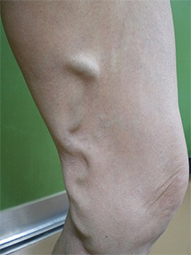

下肢静脈瘤

動脈は心臓から押し出された勢いで血液が流れていきますが、静脈にはそのような勢いがありません。筋肉の収縮と静脈に存在する逆流防止弁(一方弁)によって全身の組織から血液を心臓に戻します。その弁が種々の原因によって壊れてしまうことで、静脈血の逆流を引き起こし、静脈が瘤化していまったものを下肢静脈瘤と言います。軽症である無症状のものから、足がつりやすい、むくむ、痛いなどの症状を伴う中程度のもの、皮膚に湿疹や潰瘍ができる重症のものまであります。

当院では、最新式の下肢静脈瘤に対するレーザー治療機器ELVeSレーザー1470を使用しています。高周波治療でも治療効果はこの機器と同等と言われています。基本的には下肢静脈超音波検査、下肢単純CT撮影で手術適応、手術術式を決定しています。必要な場合には適宜検査を追加いたします。

治療法としては以下のものが考えられます。

• 弾性ストッキング:下肢の血液がうっ滞しないよう弾性ストッキングを着用します。

• 硬化療法:血管内に薬を注入し、瘤の拡大を防ぎます。

• 手術:弁が壊れてしまった静脈を抜去したり、静脈瘤を切除したりします。

• レーザー治療:静脈の内腔をレーザーにて閉塞させ、治療します。

2013年6月から、血管内レーザー治療を行っています。